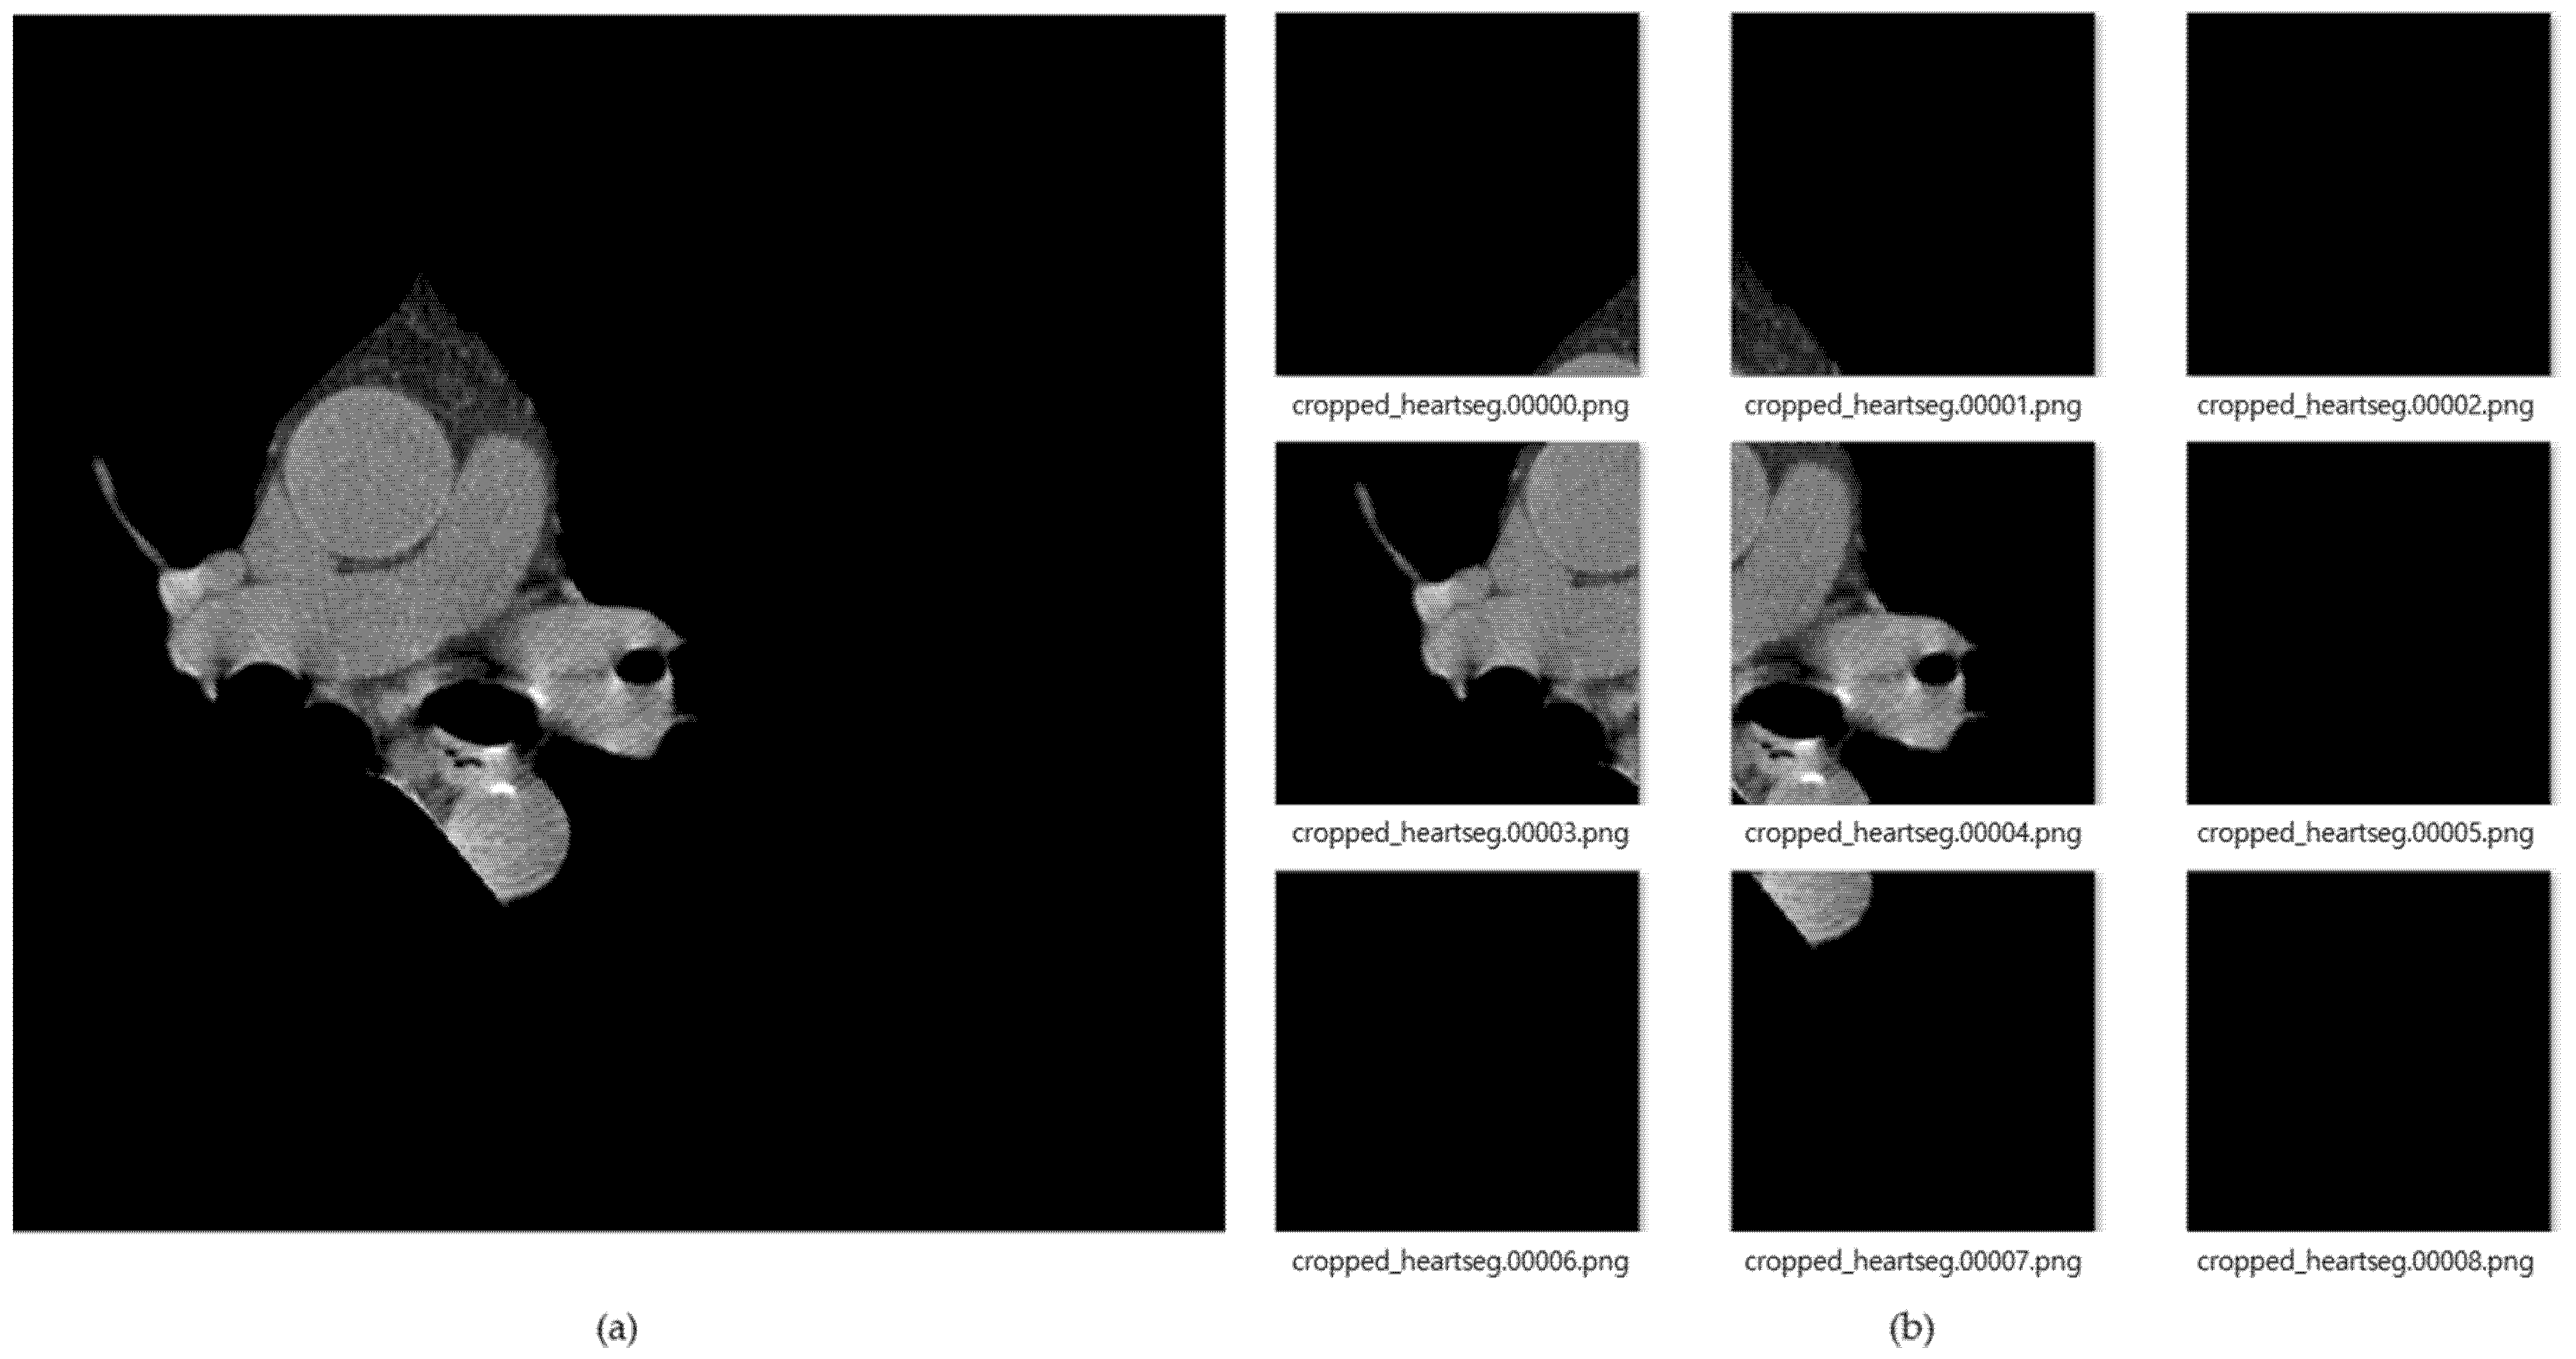

Figure 8 shows the result of images created by dividing the data into nine segments using the cardiac region segmentation data. The image data divided into nine was resized to 299 × 299 pxl size for deep-learning training. General CT images are stored as dcm file format with HU value. In this paper, we applied PNG file format with pixel values. This can be readily used for real-time labeling using a general camera, and as an assistant tool for medical doctors in the future. During data deep-learning training for this image data, there were frequent situations in which training did not proceed, due to lack of memory because of the use of many convolution layers. Therefore, we reduced the batch size to train three CNN models, and applied dropout to prevent overfitting. In the case of training accuracy and training loss, good results were obtained; but in the case of validation, splattered values occurred, due to the lack of training data. To solve this problem, the amount of data was increased by changing the angle, left, right ratio, and position values of the image through the validation generator.

Figure 8.

(a) Cardiac segmented images, and (b) cardiac cropped images created by dividing the segmented cardiac images into 9.

To find the optimal model for each image dataset, first, Figure 9 shows that when CT data was input to the current models, the highest performance was evaluated. There are cases in which calcium is formed in many areas of the entire CT image, but otherwise it occupies a very insignificant portion of the total pixels. Therefore, we constructed the most optimal dataset for training and decision by extracting only the necessary areas from the entire learning area.